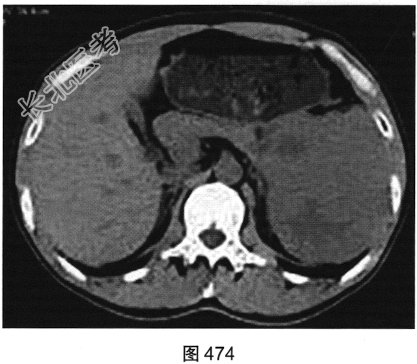

- 多项选择题3.[提示]患者行CT动态增强扫描,如图474~图476所示。对CT图像描述正确的是( )

A、脾血管被病灶侵犯

B、CT平扫呈不均匀低密度

C、胰腺被病灶侵犯

D、病灶门脉期轻度强化

E、病灶边界清晰,具有包膜

F、病灶动脉期无强化